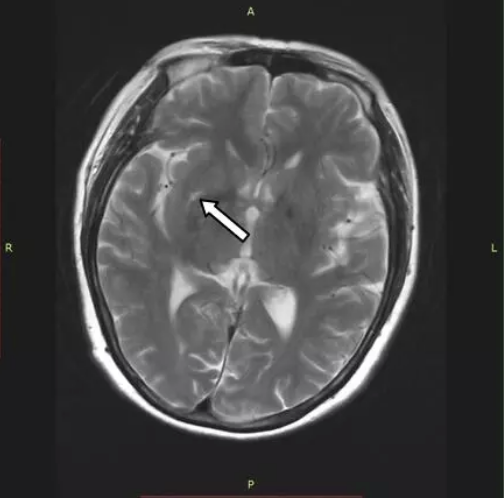

入院3天后患者诉症状减轻,复测心电图恢复正常,完善动态心电图未见明显异常。追问病史,患者自诉有长期“偏头痛”病史,行头颅MRI,提示双侧侧脑室旁散在点状缺血灶;考虑脑梗塞病变(图3)。

图3 头颅MRI